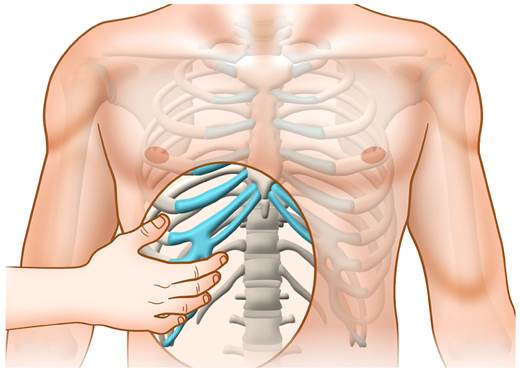

En la EF, el signo más útil es la maniobra del gancho (hook maneuver)91977. Para hacerla, el médico o la médica debe colocar sus manos sobre el borde inferior de los arcos costales inferiores del lado afectado y traccionar en sentido anterosuperior con ambas manos (figura 1). Se considera positiva si reproduce la clínica o el chasquido6.